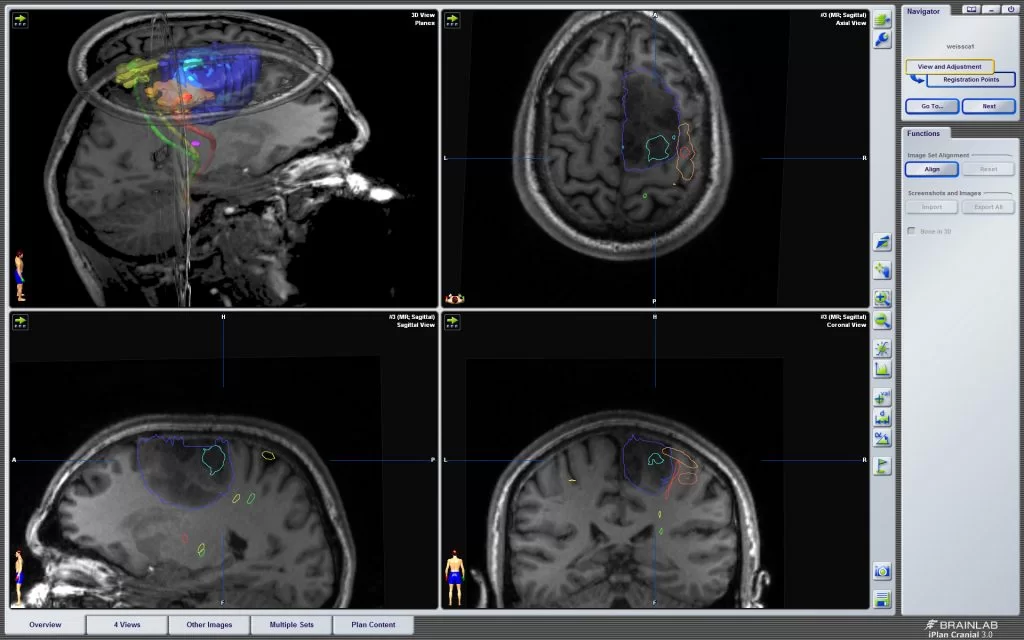

Περιλαμβάνει διάφορες τεχνικές όπως τη μαγνητική τομογραφία με ειδικές ακολουθίες (λειτουργική μαγνητική τομογραφία – fMRI), την ηλεκτρική διέγερση του εγκεφάλου, το διακρανιακό μαγνητικό συντονισμό κ.α.

Μερικοί όγκοι του εγκεφάλου αναπτύσσονται ή/και επεκτείνονται σε περιοχές του εγκεφάλου οι οποίες είναι κρίσιμες (eloquent), με την έννοια ότι ενδέχεται να περιέχουν σημαντικές λειτουργίες όπως για παράδειγμα η κίνηση και ο λόγος. Είναι σημαντικό ο χειρουργός να γνωρίζει πρίν το χειρουργείο αλλά και κατά τη διάρκεια της επέμβασης που ακριβώς βρίσκονται αυτές οι περιοχές σε σχέση με τον όγκο, προκειμένω να αποφύγει να προκαλέσει βλάβη.

Η μέθοδος της προεγχειρητικής χαρτογράφησης του εγκεφάλου συνδυάζεται συχνά με τον διεγχειρητικό νευροφυσιολογικό έλεγχο. Ο συνδυασμός των δύο τεχνικών αυξάνει σημαντικά τόσο την ασφάλεια όσο και το βαθμό εξαίρεσης του όγκου.